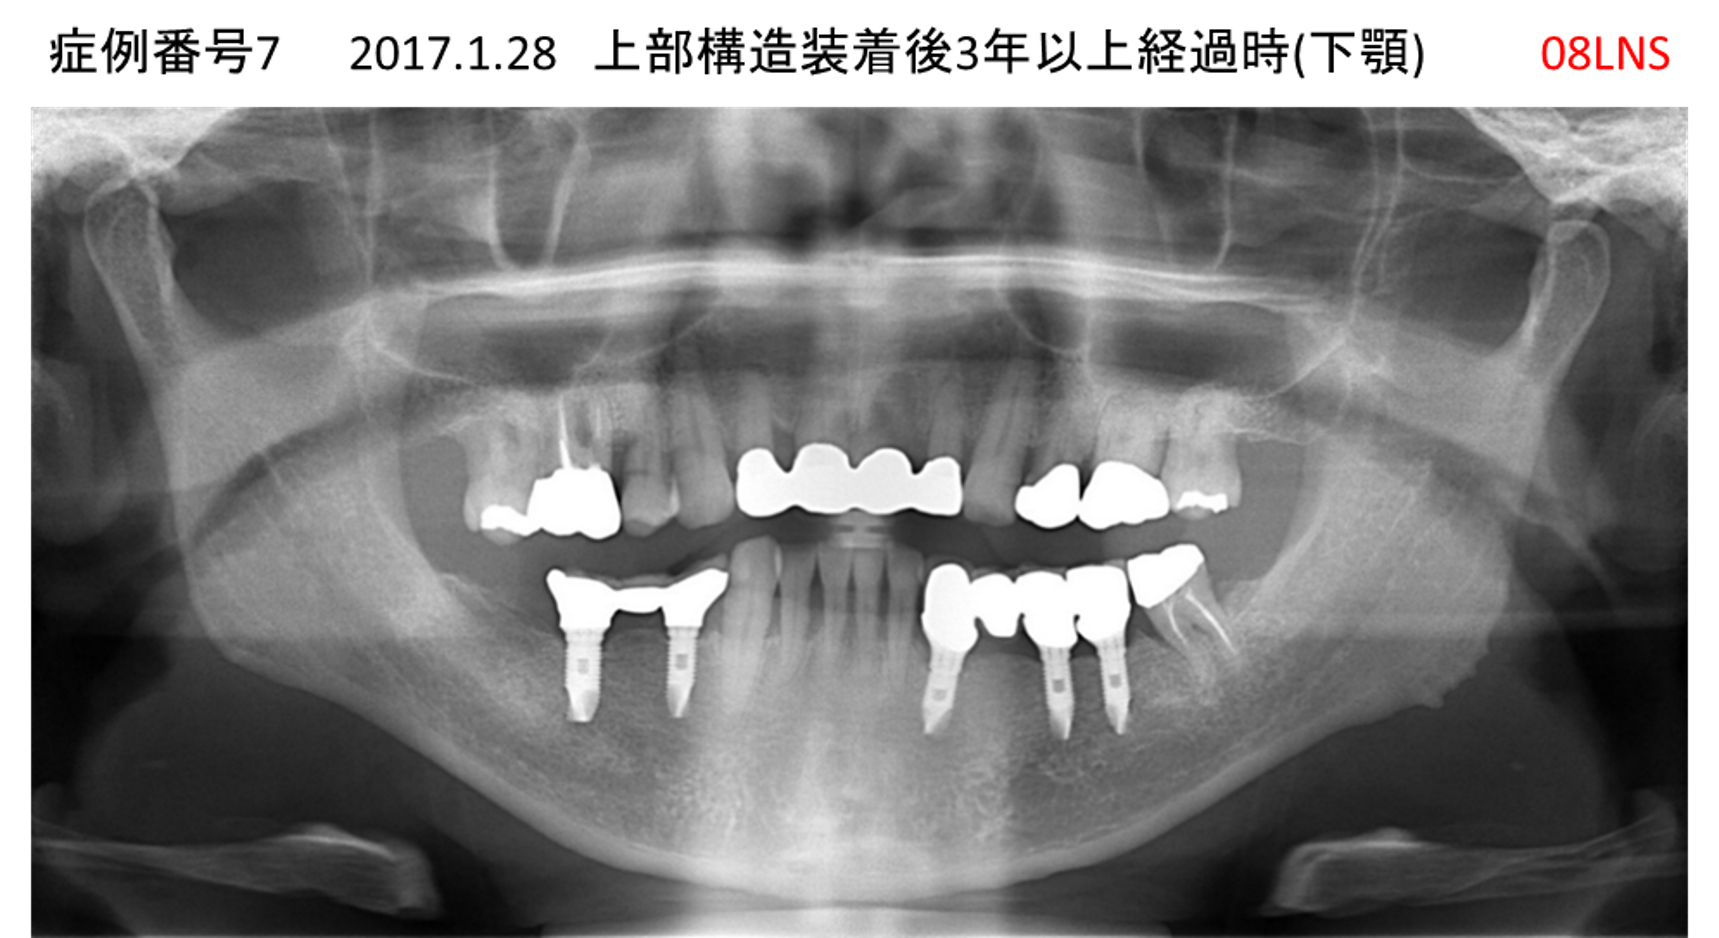

全く噛めない患者様のインプラント症例

| 治療名称 |

インプラントAGC |

| 治療費用 |

860万円+税 |

| 治療期間 |

12か月 |

| 患者さんの症状(主訴) |

全く噛めない、ごはんが後もに食べられるようになりたい、人前で口元を隠したくない |

| 治療内容 |

サイナスリフト、GBR、インプラント、AGC |

| 治療結果 |

しっかり噛めて踏ん張ることができる。食べ物をを選ばなくて済む、何でも食べられる、体重が増えた。見栄えがきれいすぎて自分じゃないみたい |

| 治療の注意点(リスク/副作用) |

インプラントが壊れたら再治療が必要 |